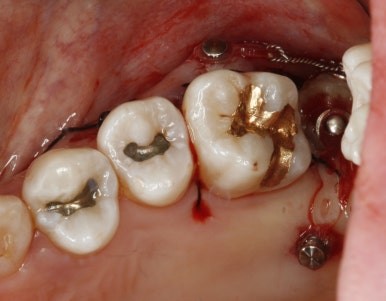

드디어 구강내로 얼굴을 내밀고 제 위치에 안착~

치료 중 임신으로 방사선 사진을 남기지 못해 아쉽지만 기능을 잘해주고 있어 뿌듯하다^^